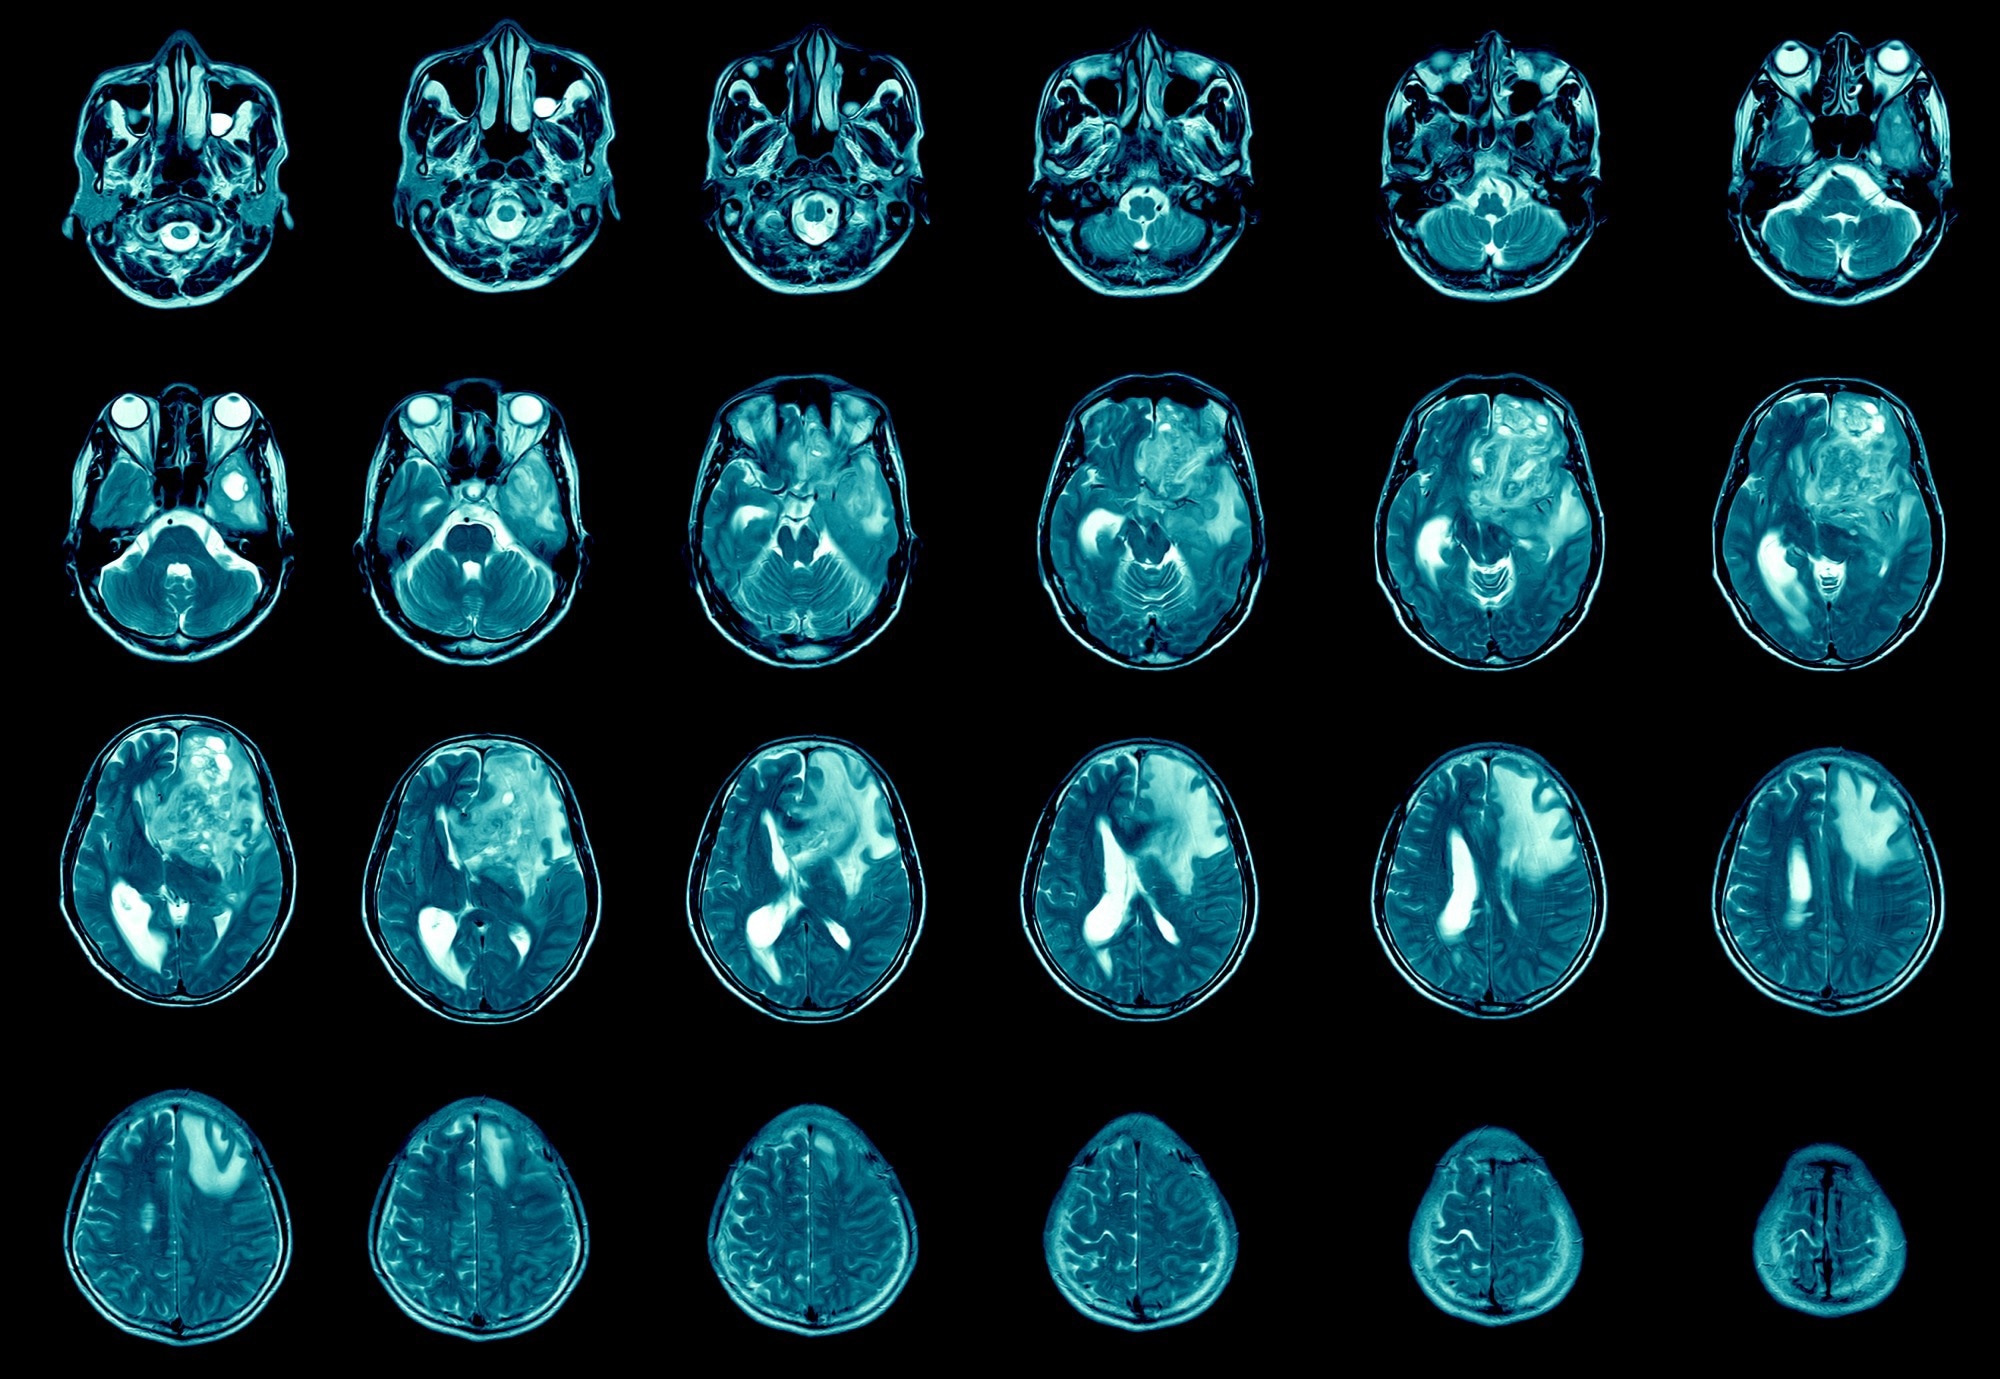

Study: A Pt(IV)-conjugated brain penetrant macrocyclic peptide shows pre-clinical efficacy in glioblastoma. Image Credit: April stock/Shutterstock

Using a four-week treatment schedule with an initial dose of 5-30 mg of the drug-conjugated peptide, the effects at its highest tolerated dose (15 mg/kg, twice weekly) on tumor growth in the GBM animal models were evaluated. Researchers conducted an MRI study during therapy (20 days post-tumor implantation) to compare tumor growth behavior between groups as the control group began to reach predetermined growth targets.